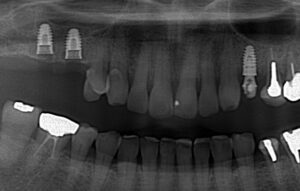

その後、さらにその奥もサイナスリフトを行いました。

青丸が骨に穴をあけた部分です。

このように奥歯にしっかりとインプラントが

入りました。

歯が増えています。